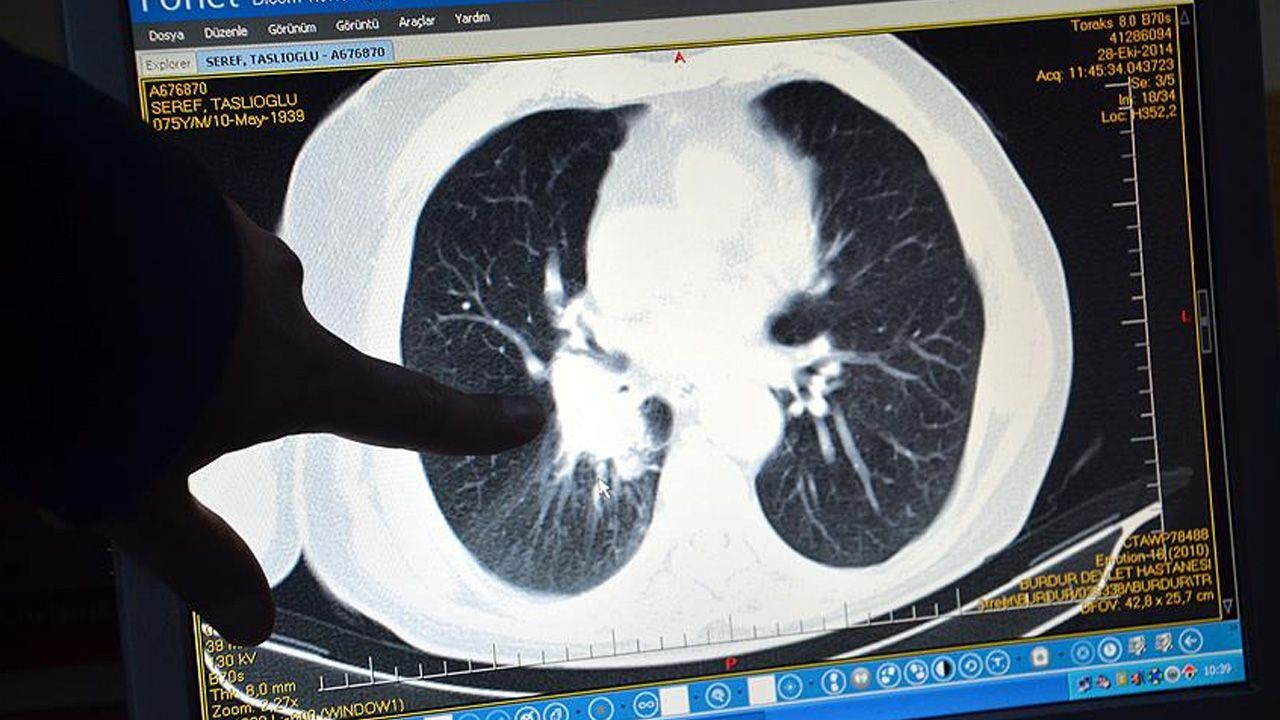

Van’da nefes darlığı şikayetiyle hastaneye başvuran 36 yaşındaki iki çocuk annesi, acil ameliyata alındı. Hastalığı ortaya çıkan kadının ameliyatı yaklaşık 4 saat sürdü. Operasyon sonrası ise sağlığına yeniden kavuşmanın mutluluğunu yaşadı.